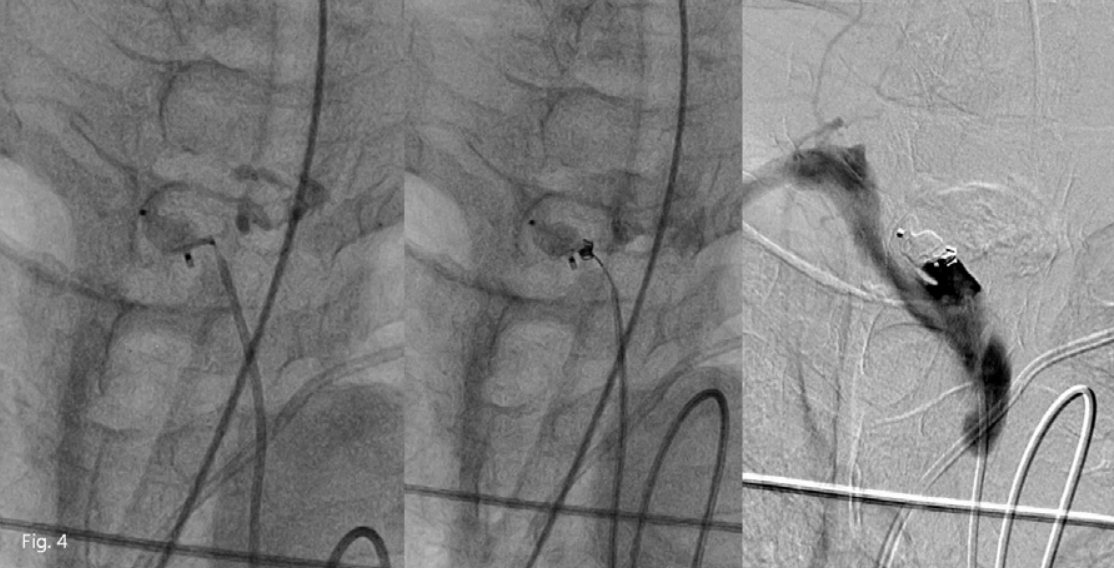

Fig. 3

Vascular plug device was applied into right proximal common carotid artery but the bleeding point seems not to be covered completely. So, placement of an additional plug device was tried to cover the residual lumen of common carotid artery, but failed.